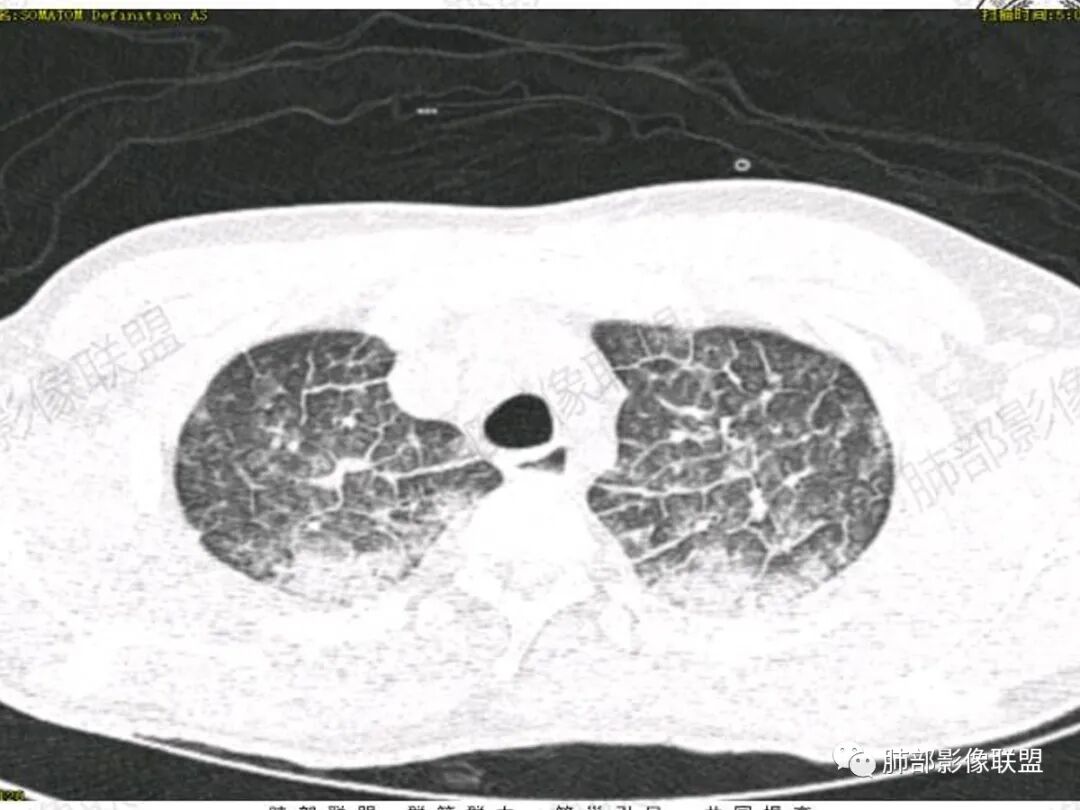

青年男性患者,气促7小时入院,白细胞及中性粒明显增高,PCT增高,CRP不高,心率快,呼吸急促,意识模糊,低氧血症,I型呼吸衰竭,PH偏低,失代偿性酸中毒,BNP偏高,胸部CT:双肺弥漫性多发斑片状实变密度影,双上肺明显,间质改变为主,综合:年轻男性,急性起病,迅速恶化,考虑中毒可能,鉴别:PCP,过敏,

双肺上叶,下叶背段多发斑片状实变影,以胸膜下分布为主,部分重力作用,以背侧为主,部分小叶间质增厚,部分周围伴有散在磨玻璃影,边界欠清,临床急性病程,血象增及PCT明显增高,意识模糊,考虑:吸入性肺炎?鉴别:AHP?CEP?PCP

37岁男性 气促 两肺对称分布磨玻璃及小叶间隔增厚,两肺上叶后段及下叶背段为著,有重力分布,下部密度较高,请结合病史排查肺水肿,理化性肺泡损伤

双肺叶透亮度对称性减低,呈磨砂状,小叶间隔规则增厚,上叶为甚,左右肺叶中轴间质增厚(示淋巴回流障碍),双肺叶弥散磨GGO征,以肺腺泡分布,双肺上,下叶融合片状,有重力分布特点,心脏大,肺动脉干增粗,首选心源性肺水肿,但无胸腔积液。与急性肺损伤和ARDS鉴别

影像:两肺上叶小叶间隔增厚,斑片,腺泡结节,重力分布,下肺不累及

双肺弥漫性病变以上肺,向心性,背部分布为主,肺动脉干无增粗,急性起病,典型的吸入性肺炎。

青年男性,气促7小时入院,意识模糊,白细胞及中性粒明显增高,PCT增高,CRP不高,心率快,体温正常,血压正常。胸部CT:双肺上叶小叶间隔光滑增厚,中轴间质增厚,弥漫性磨玻璃、多发斑片影,以上肺、背侧分布为主。影像表现考虑为肺水肿。病因:病史不支持肾功能衰竭、心源性、高原性肺水肿,无发热,似乎也不支持细菌、病毒、真菌等感染引起。吸入毒物?吸入水?

病灶的分布以上肺为主

确实要考虑吸入,倾向于吸入的是气体类的可能,因为朝上走

结合病史,最终诊断是 “急性烟雾吸入性肺损伤”,影像学表现主要是肺水肿及弥漫性肺泡损伤改变,因为烟雾气体吸入肺内分布以上肺显著,因此影像学表现也是累及上肺更明显。损伤因素包括大量一氧化碳 二氧化碳 一氧化氮等燃烧产生的有毒气体,也有烟雾粉尘颗粒对气道黏膜的损伤。